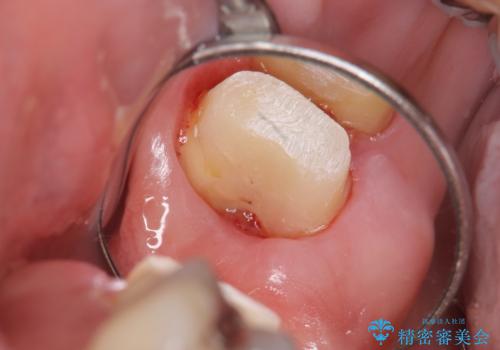

- 銀歯をやりかえたいが他院で抜歯と言われセカンドオピニオンで来院。適合の悪い被せ物が入っており、まずは古い材料、虫歯をとり保存可能か確かめる必要があり、拡大鏡下で全て取り除いたら歯質が歯茎の中まで虫歯がありました。このまま無理やり型取りをして被せ物を作っても不適合な被せ物が入る可能性が高いため歯茎を切り取る手術(ディスタルウェッジ)を行いました。そして再根管治療を行いゴールドの被せ物で治療を行いました。